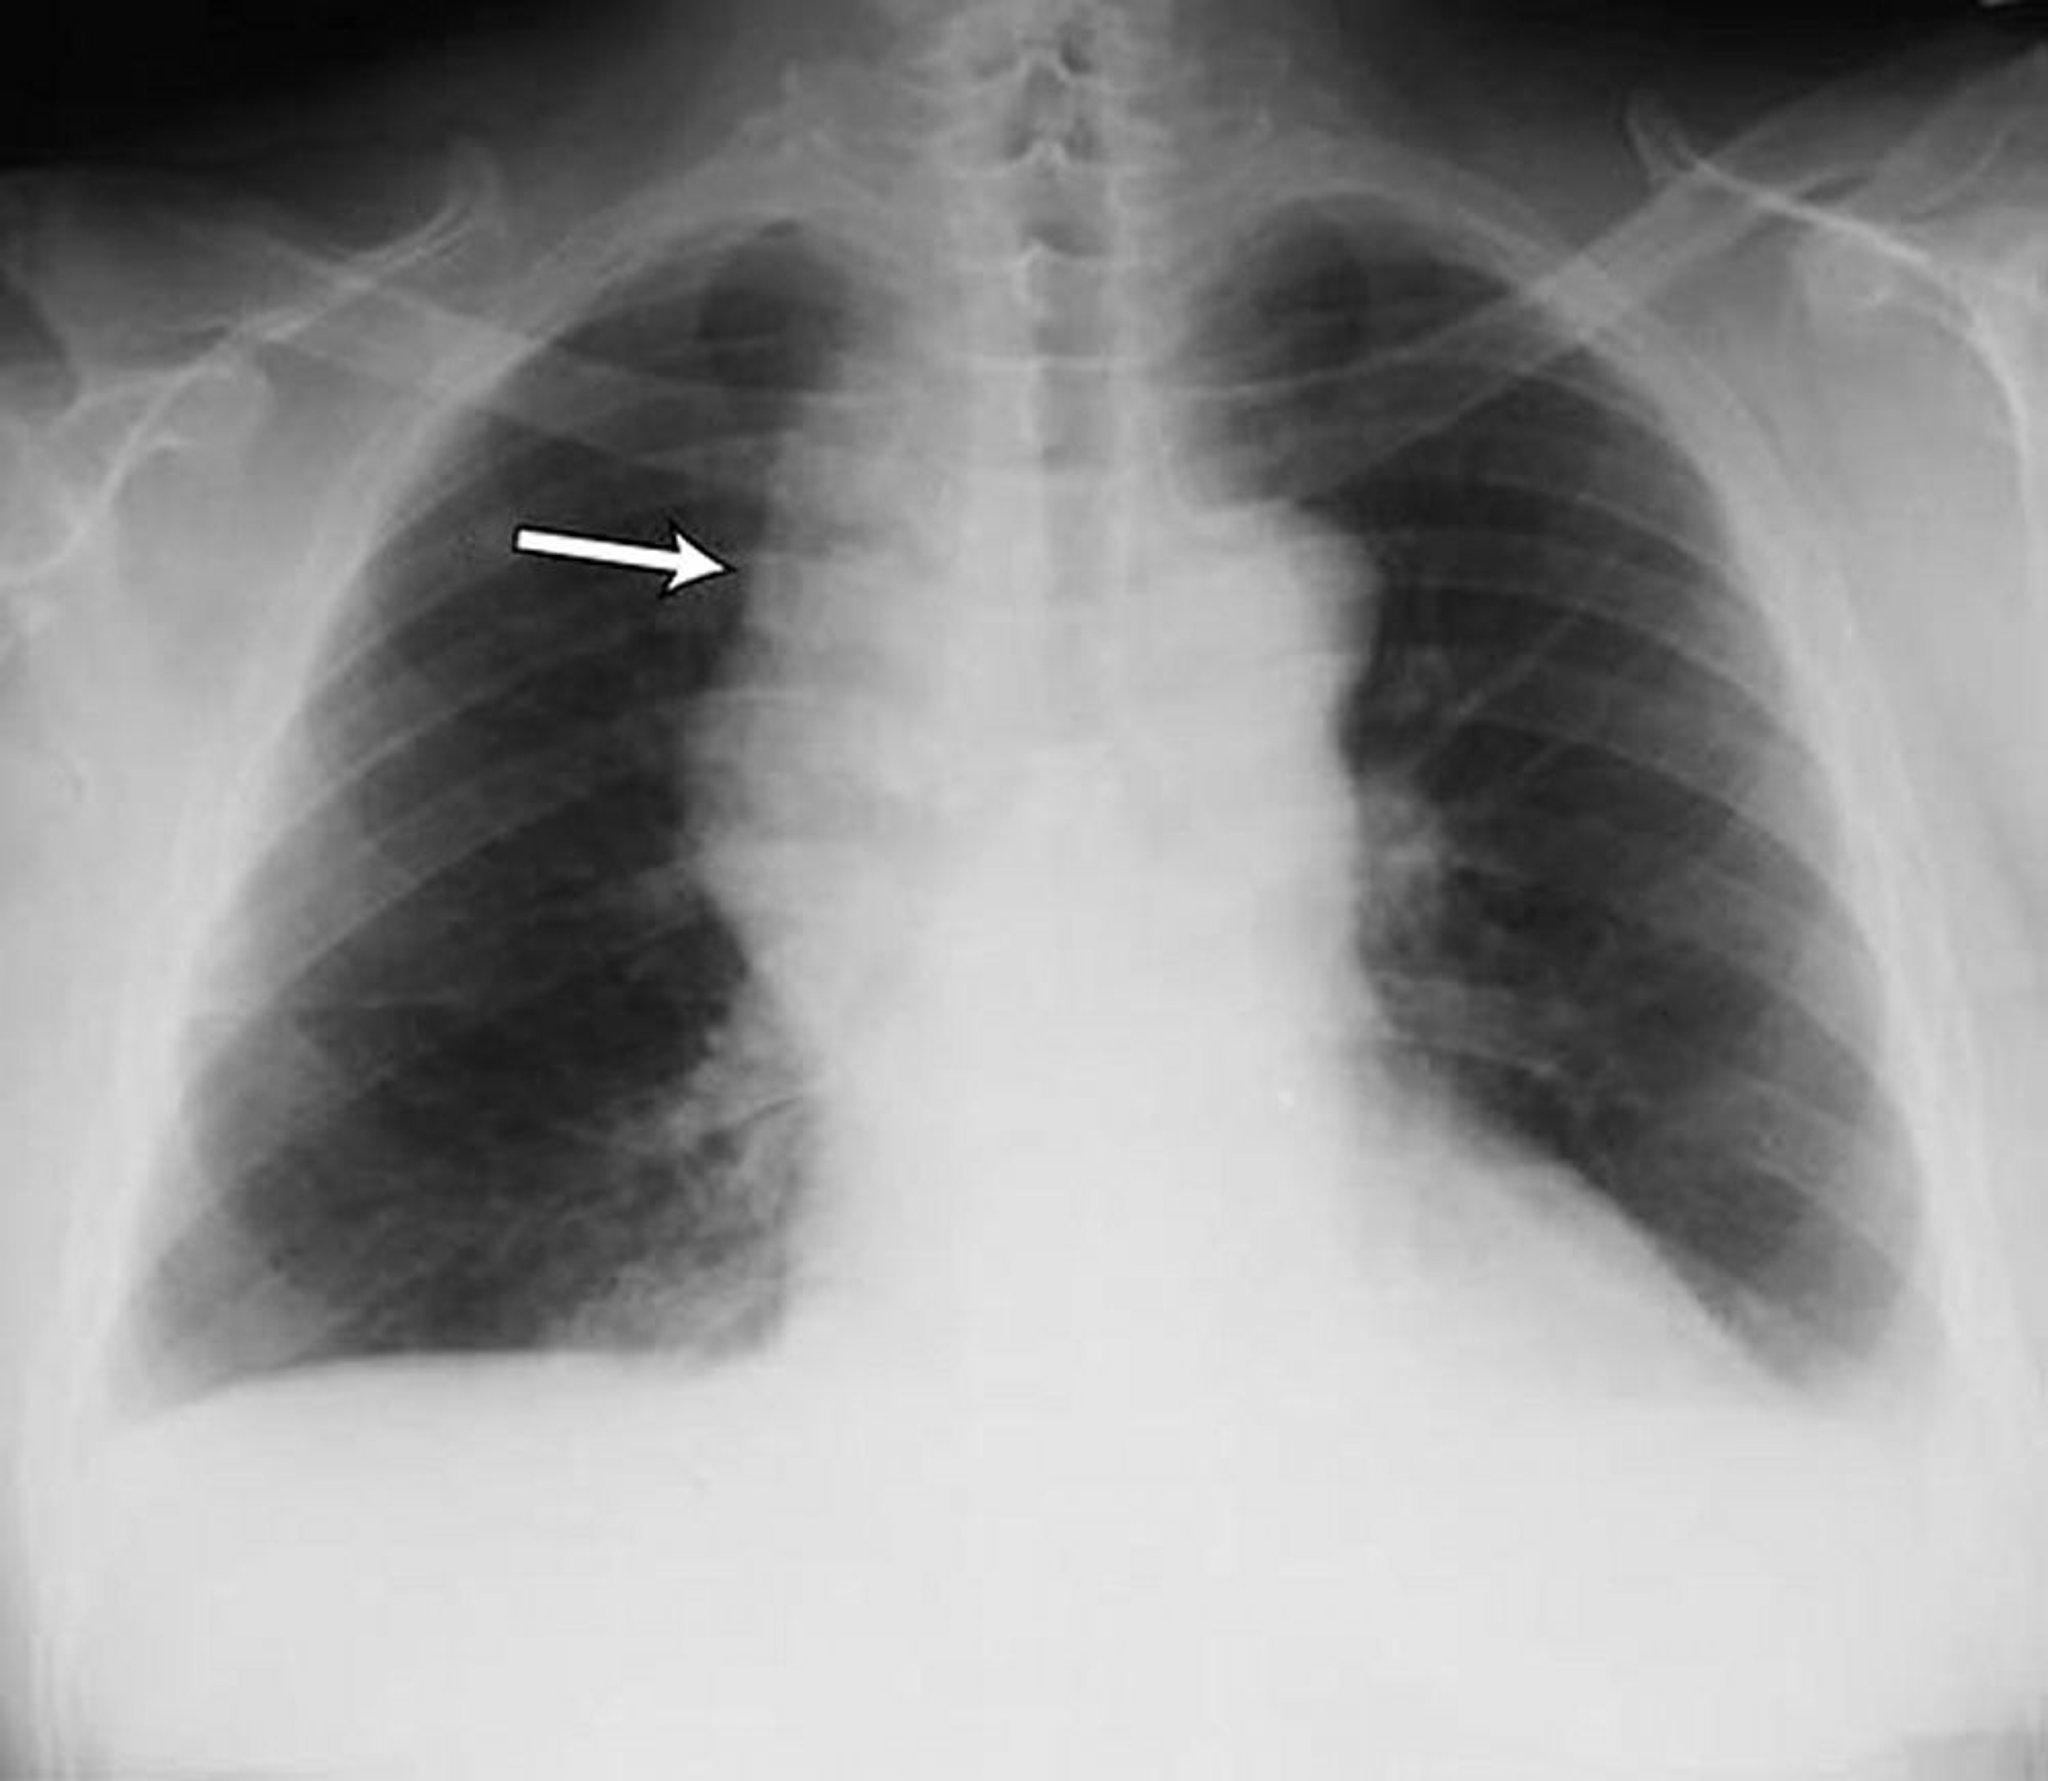

Наявність випоту

Chest radiograph is the first test performed to confirm the presence of pleural fluid. The lateral upright chest radiograph should be examined when a pleural effusion is suspected. In an upright radiograph, 75 mL of fluid blunts the posterior costophrenic angle. Blunting of the lateral costophrenic angle usually requires about 175 mL but may take as much as 500 mL. Lateral decubitus radiographs (with the side of the effusion down) may be able to detect small fluid volumes more easily than standard upright radiographs, particularly with a free-flowing effusion. Larger pleural effusions opacify portions of the hemithorax and may cause mediastinal shift; effusions > 4 L may cause complete opacification of the hemithorax and mediastinal shift to the contralateral side.

Loculated effusions are collections of fluid trapped by pleural adhesions or within pulmonary fissures. Further imaging (lateral decubitus radiographs, chest CT, or ultrasound) should be performed if it is unclear whether a radiographic density represents fluid or parenchymal infiltrates or whether suspected fluid is loculated or free-flowing; these tests are more sensitive than upright radiographs and can detect small fluid volumes. Loculated effusions, particularly those in the horizontal or oblique fissure, can be confused with a solid pulmonary mass (pseudotumor). They may change shape and size with changes in the patient’s position and the amount of pleural fluid.